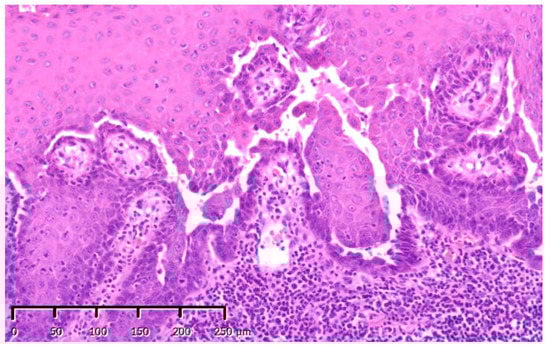

| 9 | Biopsy (Figure 4), | SBCWPV, OWS, NM (fourth) | ||

| HBO (20 times) | ||||